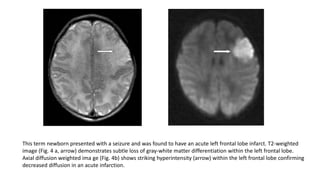

This term newborn presented with a seizure and was found to have an acute left frontal lobe infarct. T2-weighted

image (Fig. 4 a, arrow) demonstrates subtle loss of gray-white matter differentiation within the left frontal lobe.

Axial diffusion weighted ima ge (Fig. 4b) shows striking hyperintensity (arrow) within the left frontal lobe confirming

decreased diffusion in an acute infarction.